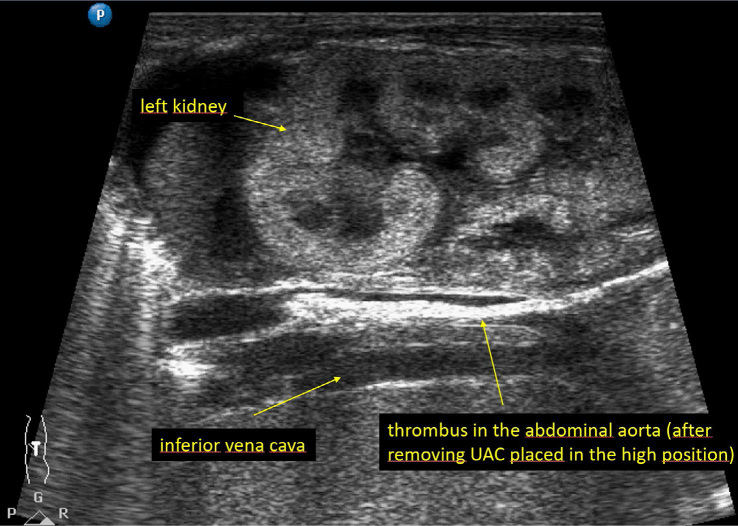

Results: The incidence of thrombosis requiring anticoagulant treatment was 22% in neonates with an umbilical artery catheter in the standard position. No thrombosis was detected in those with an umbilical artery catheter placed in the ultralow position. The study and control groups had similar catheter indwelling times (mean, 8.2 ± 4.1 vs. 8.5 ± 4.0 days, p = 0.687).

Conclusions: This is the first report to present a novel position for the placement of umbilical artery catheters. The preliminary findings for the novel ultralow umbilical artery catheter position indicate that it may provide a safety benefit over the conventional umbilical artery catheter position.